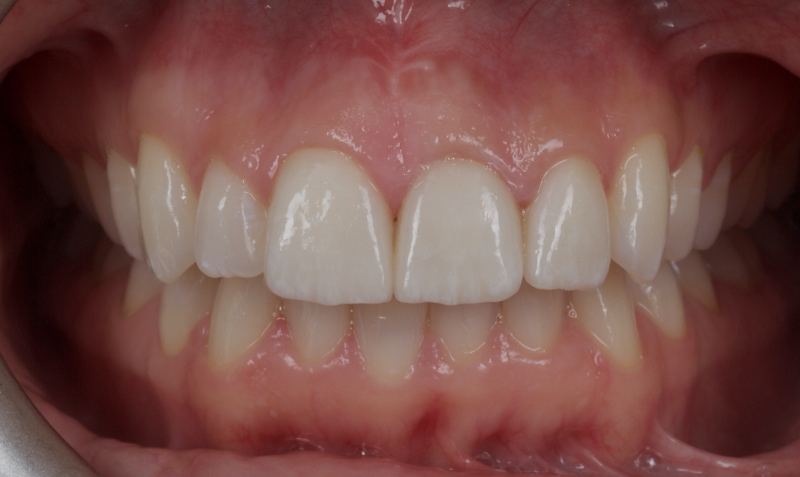

Historically, discolored anterior teeth were treated with indirect ceramic restorations, such as crowns or veneers. This can be illustrated in the case shown in Figure 1, where the discolored left central incisor (2.1), along with two other incisors, was treated with lithium disilicate ceramic veneers (Fig. 2). More recently, direct composite materials that incorporate specialized “opaquers” have also been utilized for treatment.